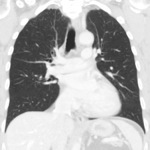

Thorax

Coronal